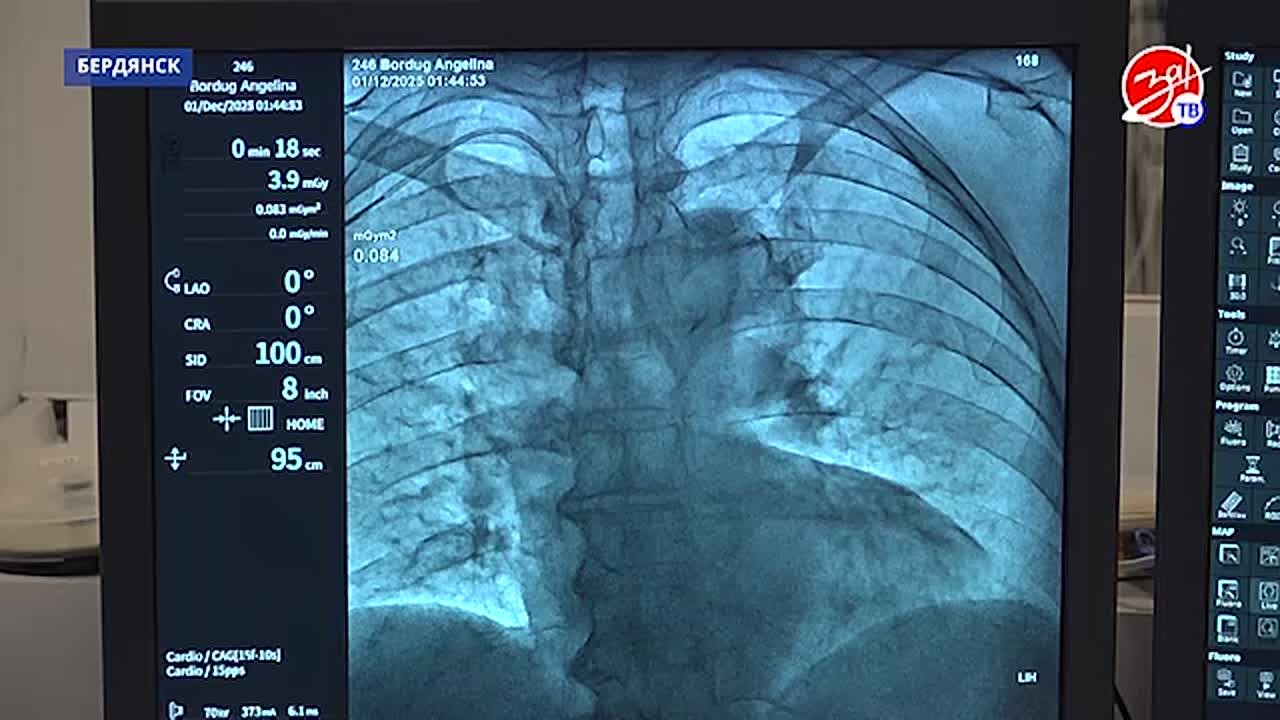

Терапевтический корпус — место, где рука об руку работают сердечно-сосудистый хирург и врач-кардиолог. В отделении аритмологии, помимо проведения плановых операций, врачи ежедневно оказывают помощь экстренным пациентам.

Для сердечно-сосудистого хирурга Ришата Шафикова первая командировка оказалась весьма плодотворной. За минувшие 3 недели он провёл 30 операций. Его коллега, врач-кардиолог Алексей Слепнев также демонстрирует хорошие результаты работы.